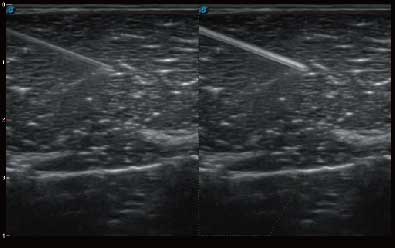

• μ-Scan微米成像技术

微米成像技术提升了对组织斑点噪声信号的抑制能力,并进一步强化边界信息,从而获得清晰图像。